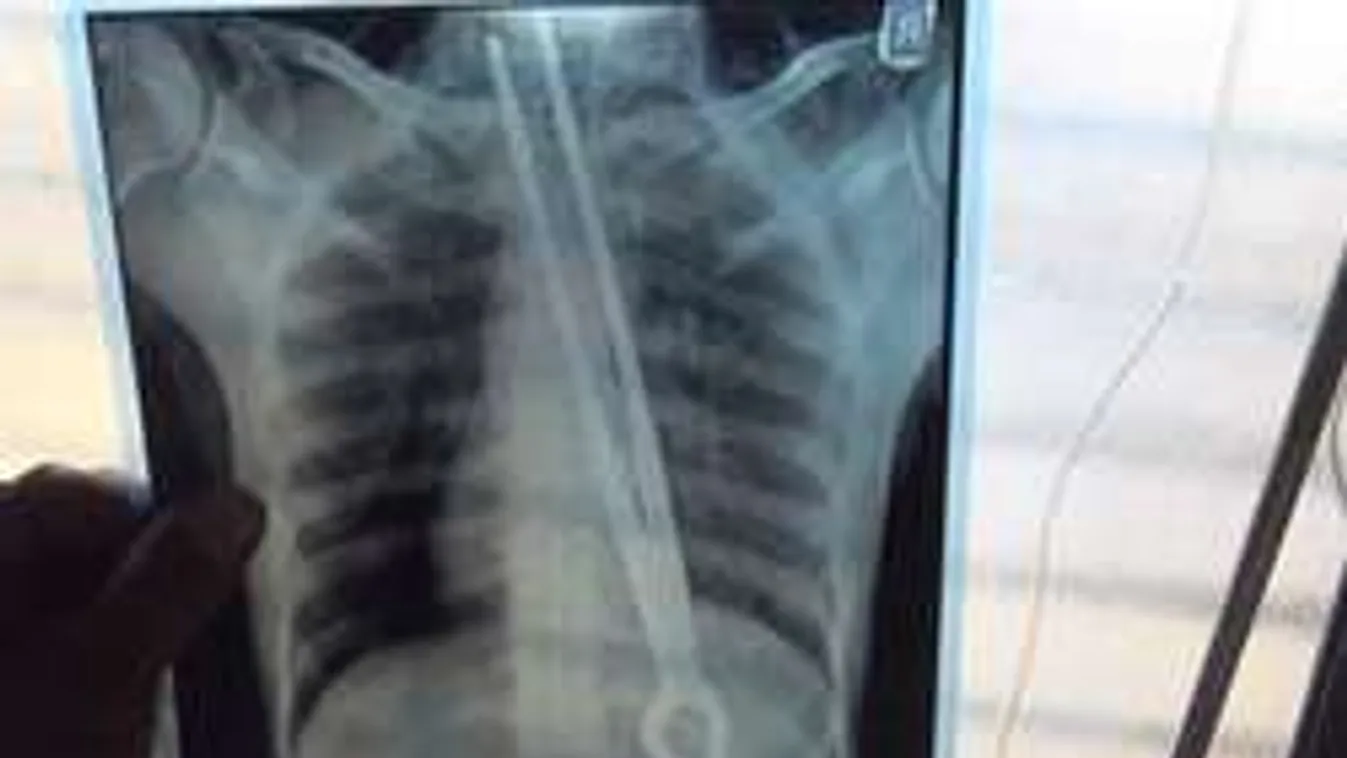

El is kezdte letuszkolni az eszközt a torkán. A fémtárgy szétroncsolta a nyelőcsövét, majd elakadt a bordáiban.

Az is csoda, hogy egyáltalán ennyire is le tudta nyelni. Négyórás műtét lett a vége. A férfi kis híján belehalt a világ leghülyébb fogadásába. Az állapota jelenleg stabil - írja a Mirror.